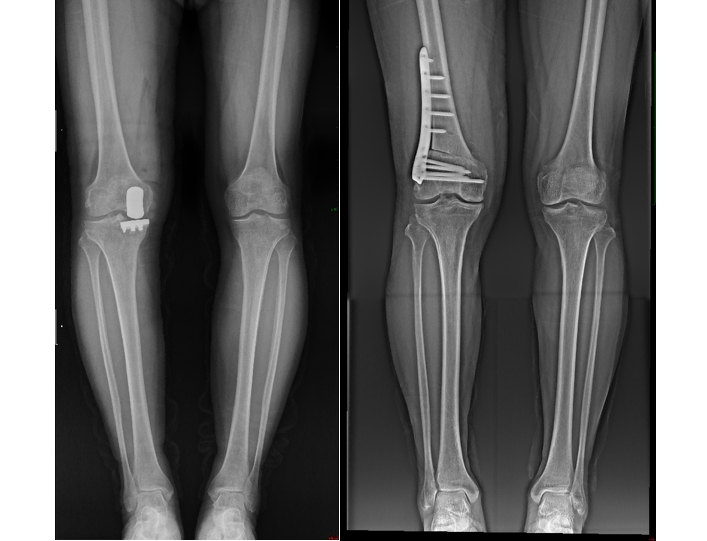

考虑到哥哥年龄偏大,且病情主要集中在膝关节内侧,内侧胫股关节面磨损严重,而外侧及前后交叉韧带功能尚好,谭红略主任团队决定为他实施单髁表面置换术。这一手术精准替换受损的膝关节部分,保留了健康组织,术后张伯伯恢复迅速,不仅疼痛大幅减轻,行走、上下楼梯等日常活动也变得轻松自如。

而对于相对年轻的弟弟,尽管同样遭受膝关节炎的困扰,但他的情况却有所不同。作为一位热爱运动、活动量较大的人,他的膝关节磨损并不均匀,且年龄尚轻,谭红略主任团队选择了股骨下端闭合截骨术。这一手术通过调整下肢力线,减轻特定区域的压力,有效延缓了关节炎的进展,同时保留了自然关节的功能。术后,弟弟不仅疼痛消失,更重要的是,他得以继续享受运动带来的快乐,生活质量显著提升。